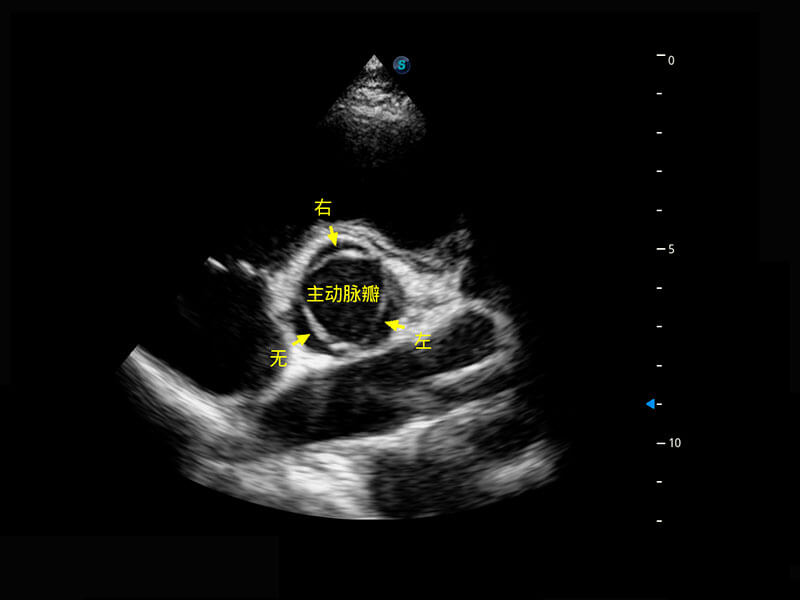

四腔切面

四腔心血流

右室双出口

P60搭载一系列胎儿心脏成像技术,实现精细的胎儿心脏评估。